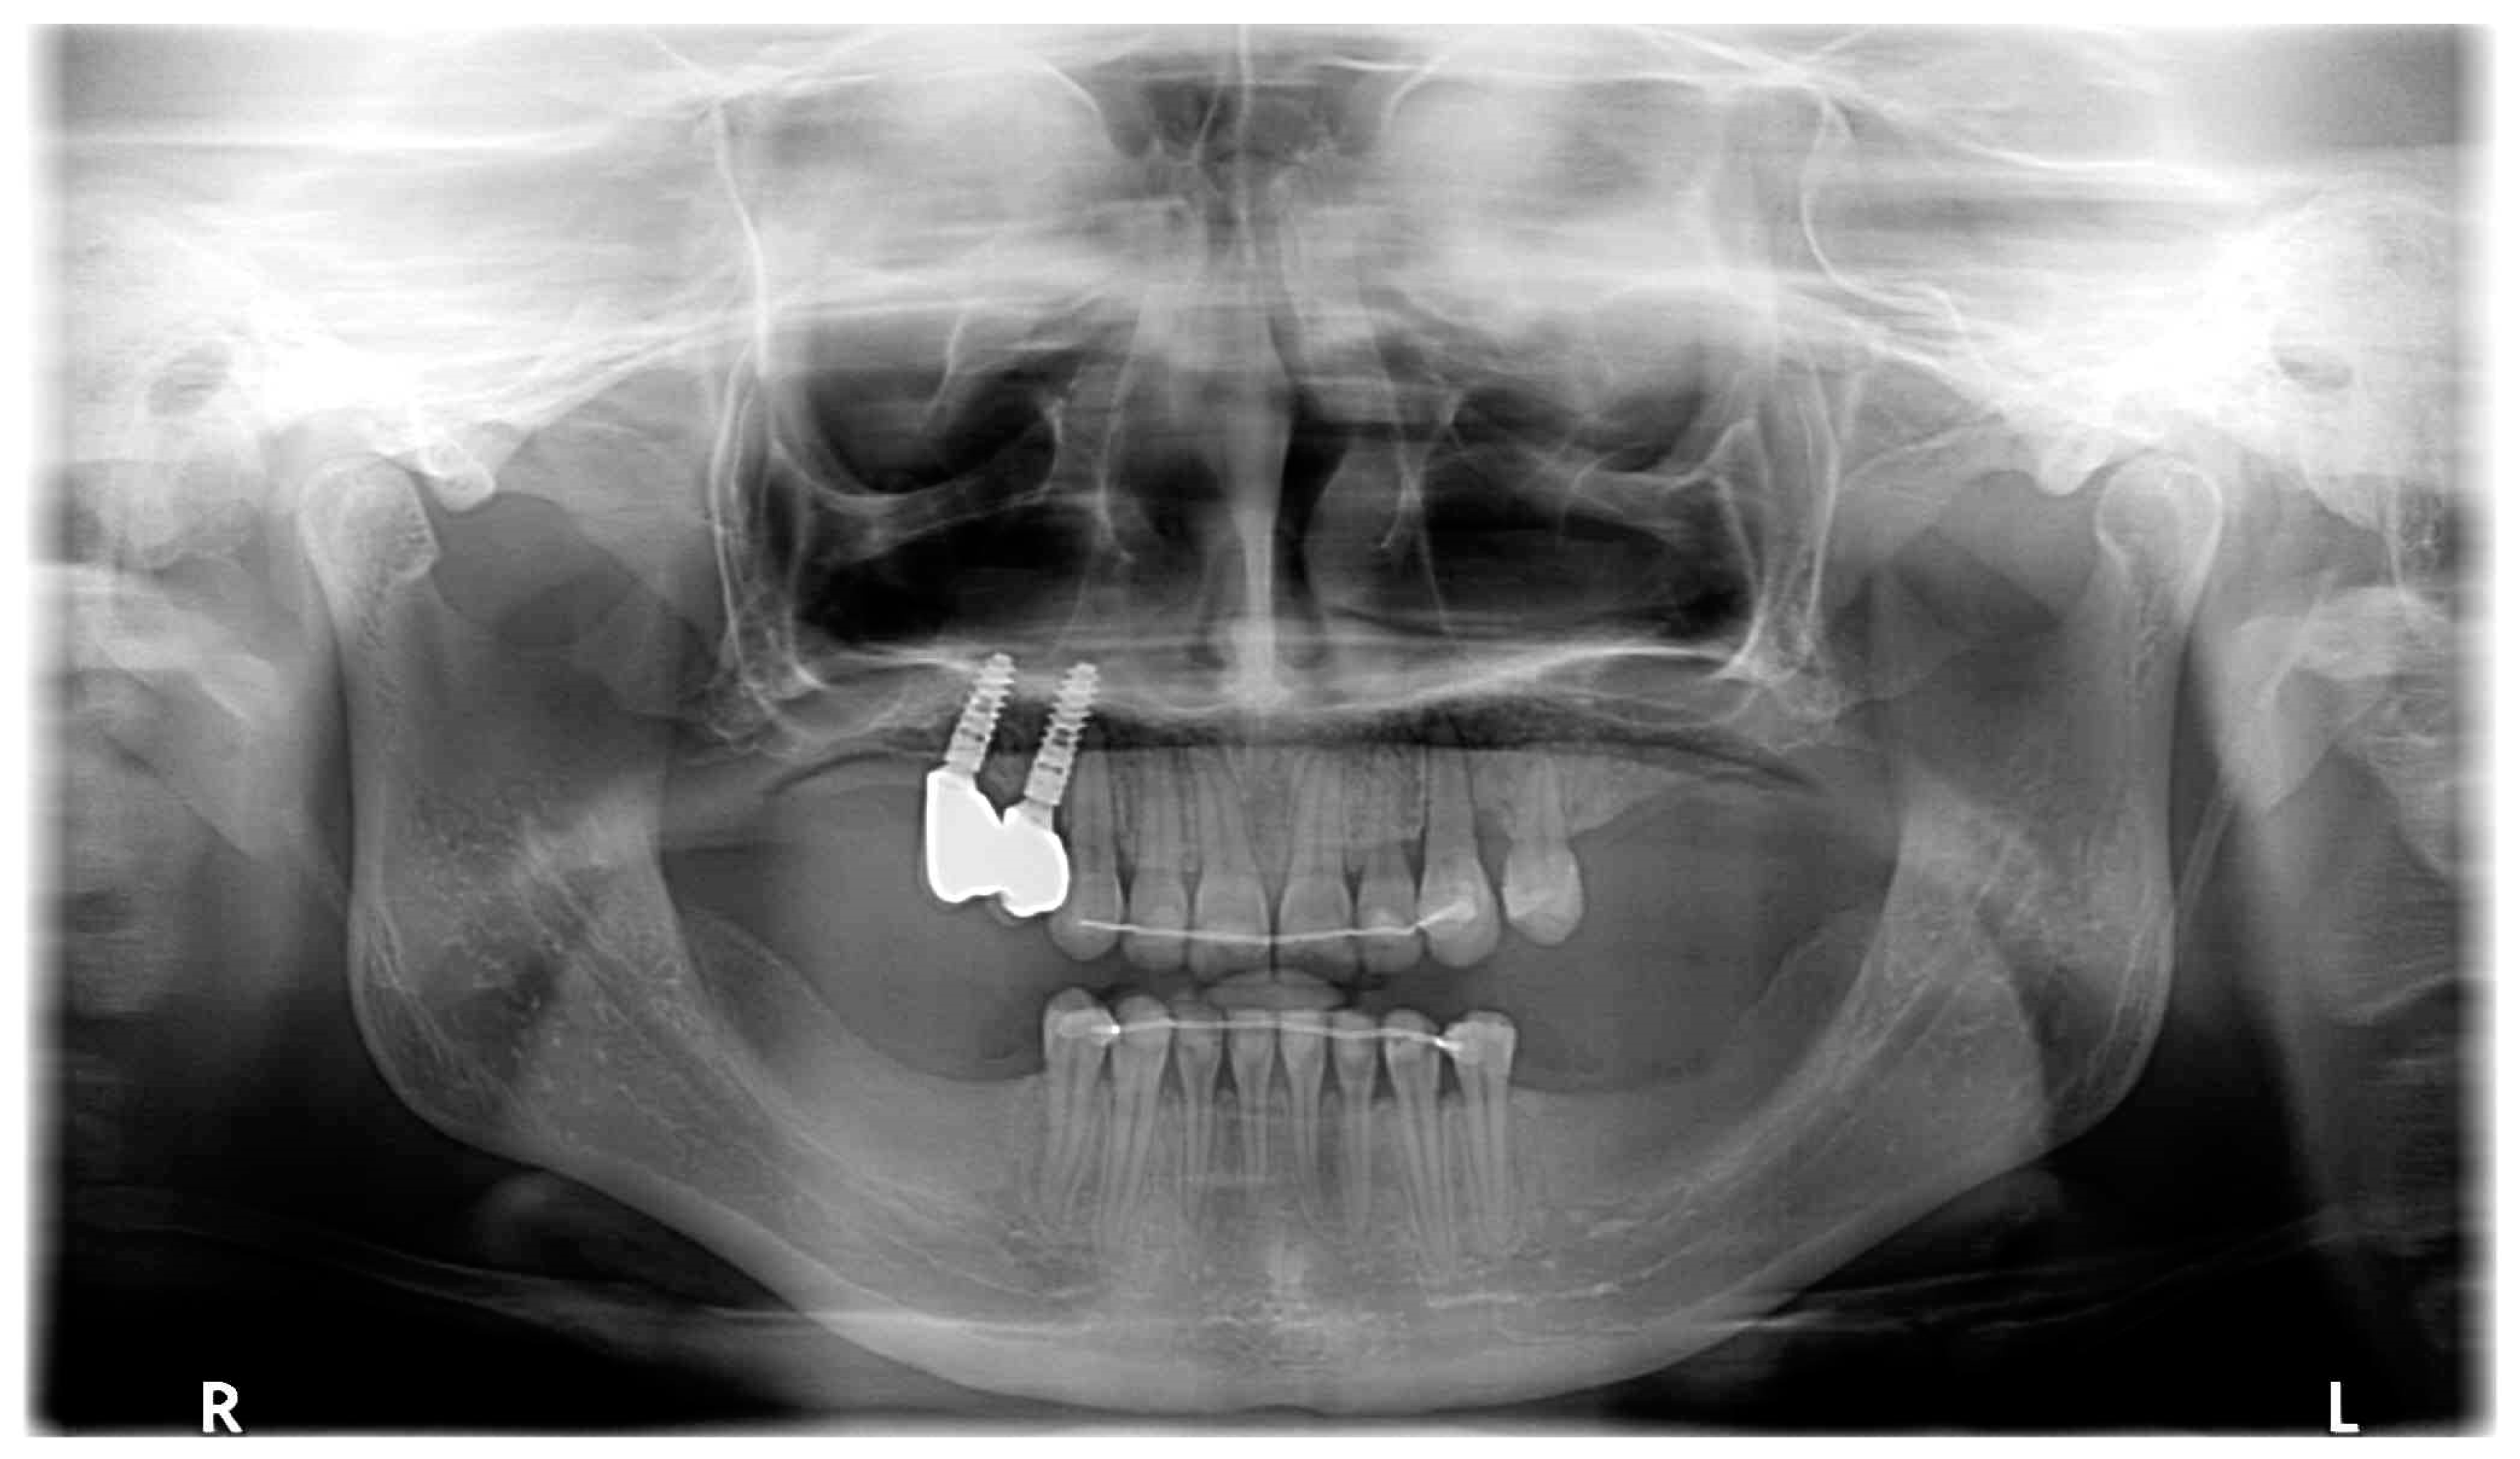

| August 2021 | Open sinus lift surgery with porcine bone-derived grafting material (The Graft™ bone substitute cancellous granules (Purgo Biologics, Seongnam, Republic of Korea) and BioCover™ resorbable collagen membrane (Purgo Biologics, Seongnam, Republic of Korea)) was performed on the right side of the maxilla. |

| March 2022 | Two dental implants were placed: tooth no. 14—Axiom® PX 3.4 × 12 mm (Anthogyr, Sallanches, France), tooth no. 15—Axiom® PX 3.4 × 10 mm (Anthogyr, Sallanches, France). |

| May–August 2022 | Finishing; control panoramic X-ray (Figure 8); 1st canine relationships and midline consistency; debonding of the brackets; fixed upper and lower retainers’ placement (0.027″ × 0.011″ 8-strand braided SS), tooth no. 24 was not fixed to the retainer due to increased mobility. |